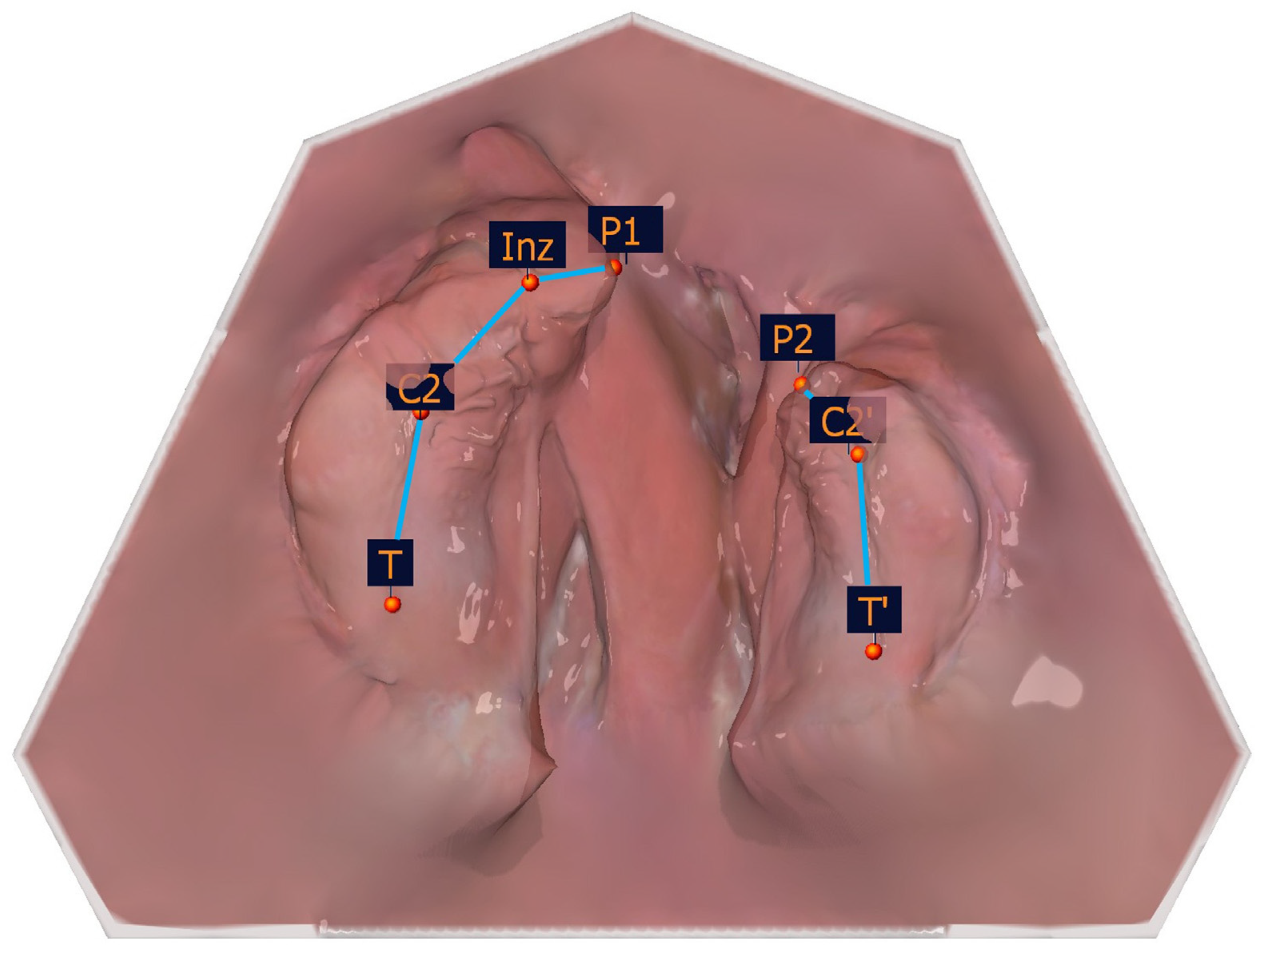

The transversal measurements are shown in Table 5 and in Figure 10.

Figure 10. Illustration of the transversal measurements.